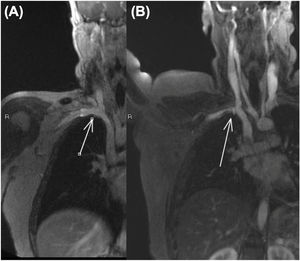

En la resonancia magnética dinámica en abducción se observó una compresión del plexo braquial y de la vena subclavia a nivel del espacio costoclavicular, que desaparecía con la postura anatómica (fig. 2).

En la resonancia magnética dinámica se observó una oclusión completa del estrecho costo-clavicular de la vena subclavia izquierda con la extremidad en abducción forzada.